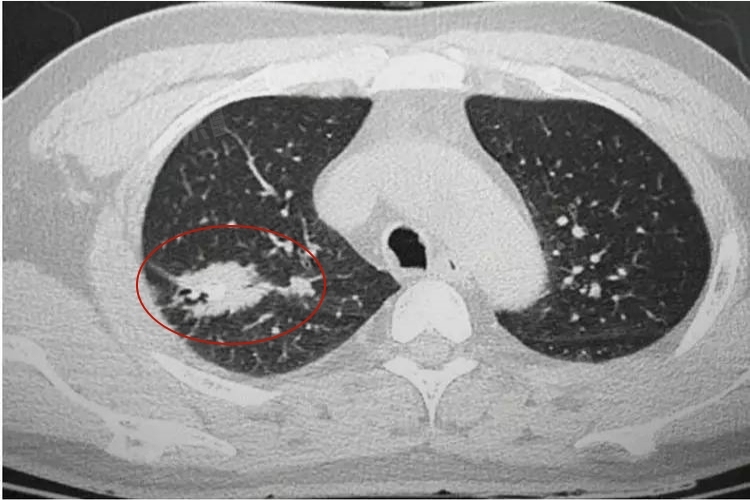

4、钙化灶合并恶性病变风险:钙化灶可能与肺癌等恶性病变有关联,特别是形态不规则、边缘模糊的钙化灶,需高度警惕。应通过进一步的检查,如CT增强扫描、穿刺活检等,明确诊断,一旦确诊恶性,需要配合医生进行抗肿瘤治疗,及时干预。